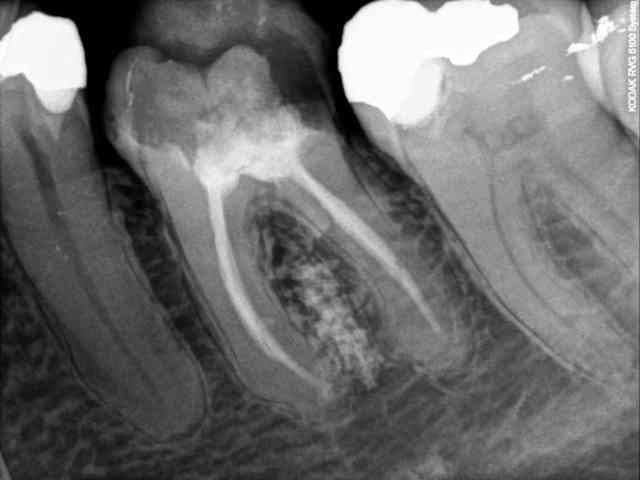

27/08/2011 à 12h59

Radio post-bourde :

R3 l4egli - Eugenol

Montre-nous l'ostéointégration de ton implant composite dans 3 mois ;)

Ah ouais quand même! Quelqu'un connait les conséquences de particules composite dans la circulation? Il est flow et pas du tout polymérisé, et dans le noir? Je sais pas si j'attendrais beaucoup avant extraction quand même...

Je vois pas comment ça pourrait bien se passer...

La perfo en elle même à environ 30% de chance de guérir avec un pronostic à long terme pas terrible...

Pour le compo, là tu viens de faire une expérience originale.

Quand on pense que ces matériaux n'ont même pas d'AMM... :)

Ce serait ma patiente, j'extrait, je nettoie, et j'offre l'implant, la couronne qui était prévu restant à sa charge...

Le risque c'est quand même une belle infection avec perte osseuse plus ou moins importante avec du compo qui va se balader on ne sait où....